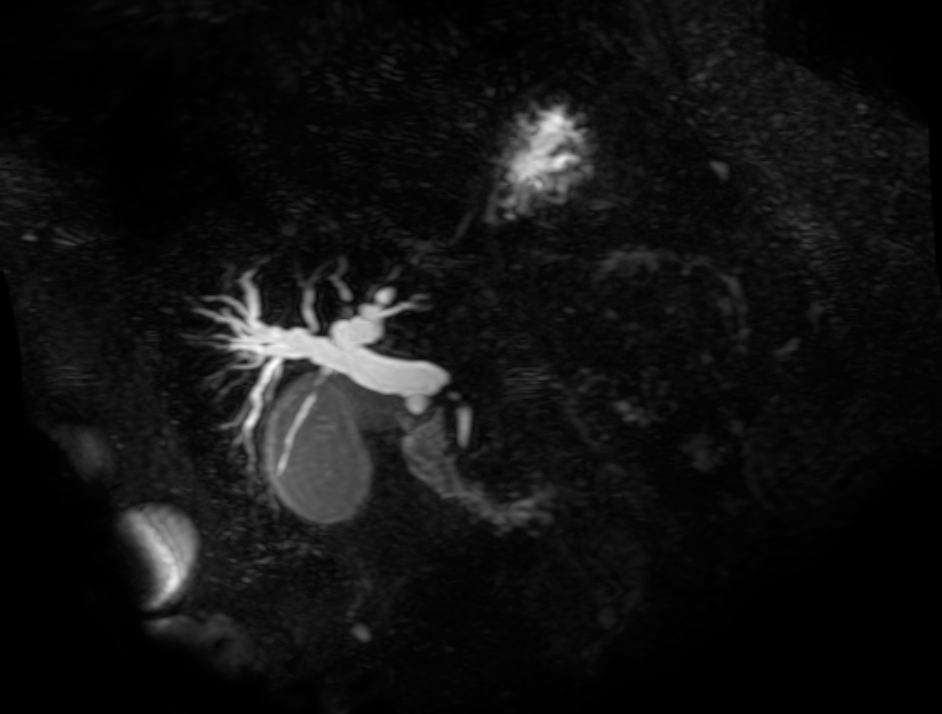

From www.wjgnet.com